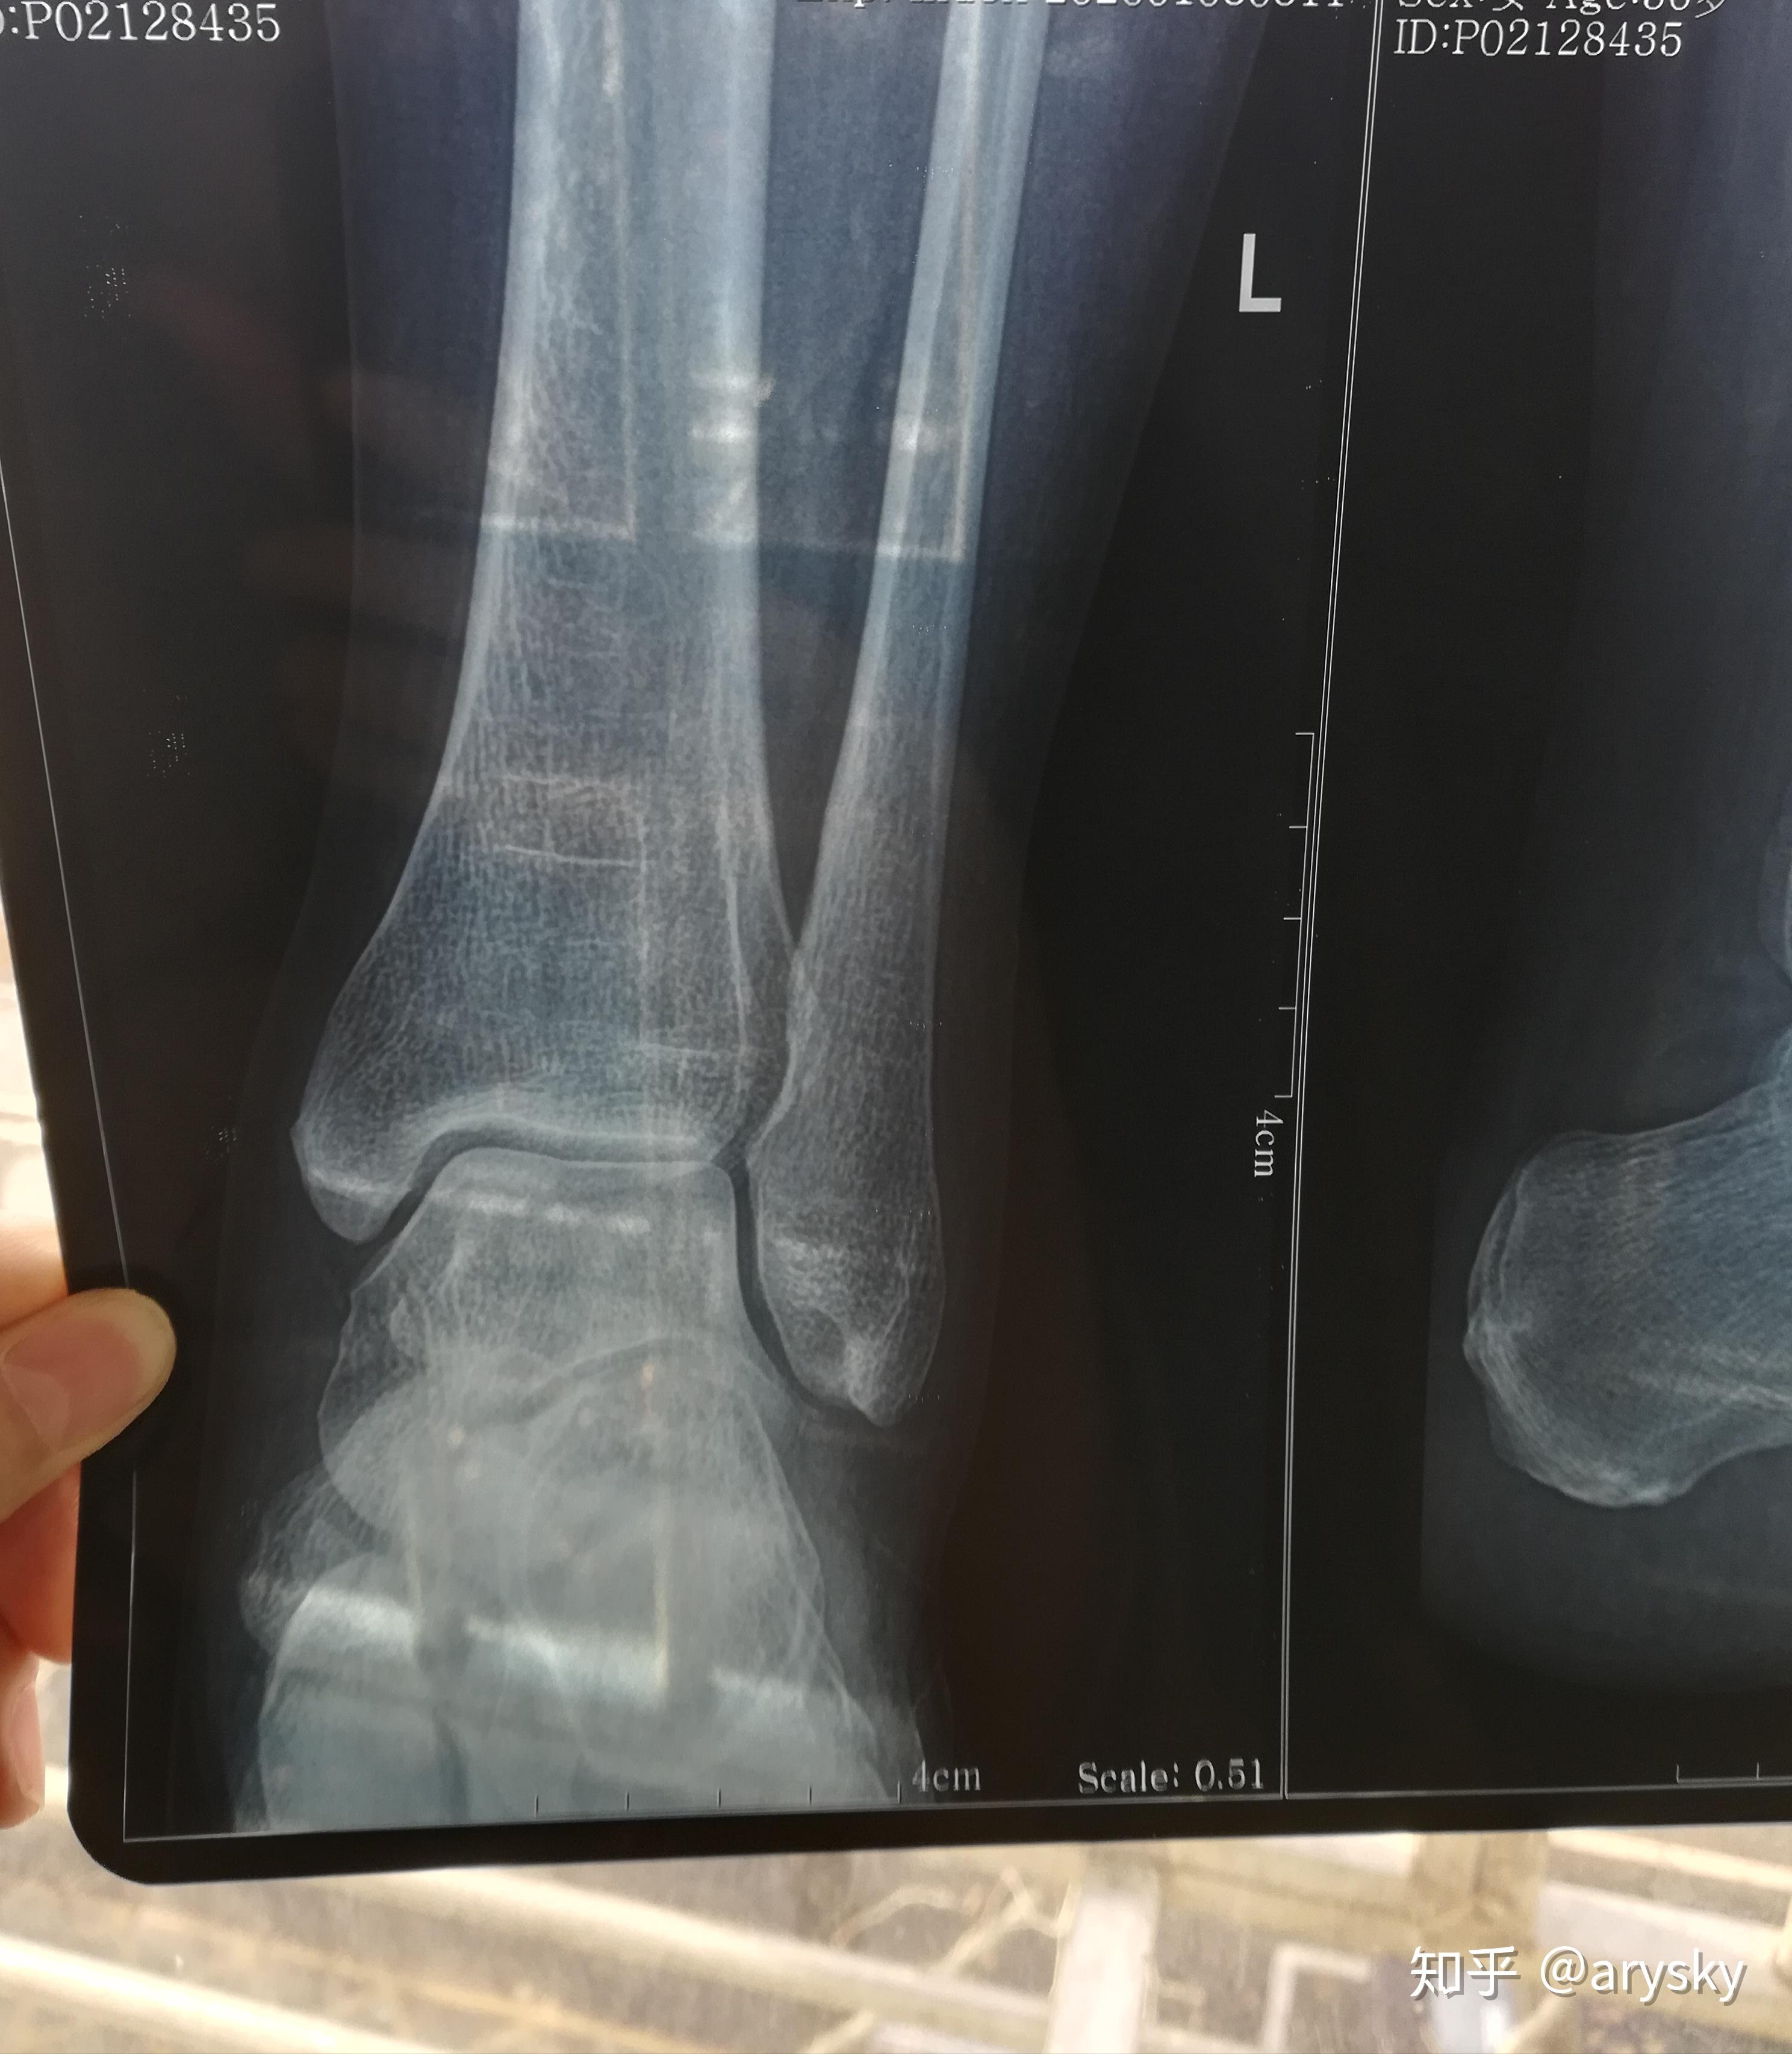

19年1127号左外踝撕脱性骨折